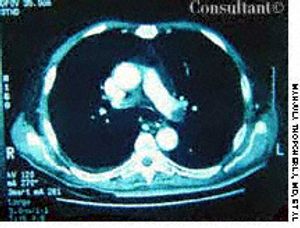

A 52-year-old woman who was undergoing chemotherapy for lymphoma was admitted to the hospital with fever of a few days' duration. The patient had smoked cigarettes for many years; she had no history of deep venous thrombosis.